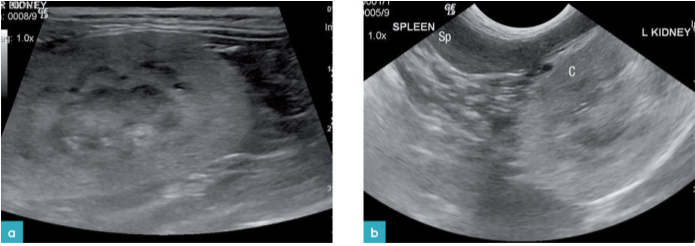

在诸如淋巴瘤和转移性鳞状细胞癌等肿瘤中,可以看到回声增强及皮质神经元分化明显(图14和15)。尽管偶尔会有肾脏减小的现象,但通常观察到的是肾脏肿大。据报道在淋巴瘤病例中,皮质周围会有低回声晕。这种晕圈可以与肾周围积液区别开来,因为其只在皮质周围才能看见,而在其余的腹膜后间隙则观察不到。